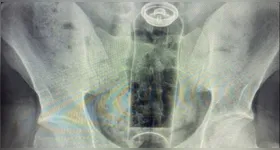

objetos estranhos